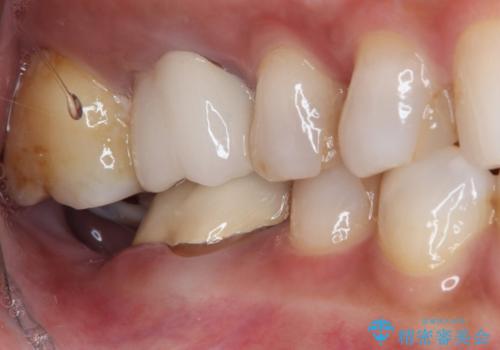

- 10年以上前に装着した奥の銀歯が目立つので白くしたいとのことで来院された患者様です。

痛みなどの症状はありませんでしたが、レントゲン写真から元々のむし歯が大きかったことが予想されました。

神経近くまでむし歯が及んでることと、舌が大きく損傷の可能性があることから、ダムプロテクターを装着した状態で処置を行うこととしました。

仮歯装着後、症状がないことを確認して、オールセラミッククラウンにて補綴することとしました。

レントゲン写真で想像していた以上にむし歯が大きかったため、痛みが出てしまう危険性がありましたが、術後の経過は非常に良好です。

長年気にされていた目立つ銀歯が自然な歯に仕上がり、患者様には大変満足していただきました。